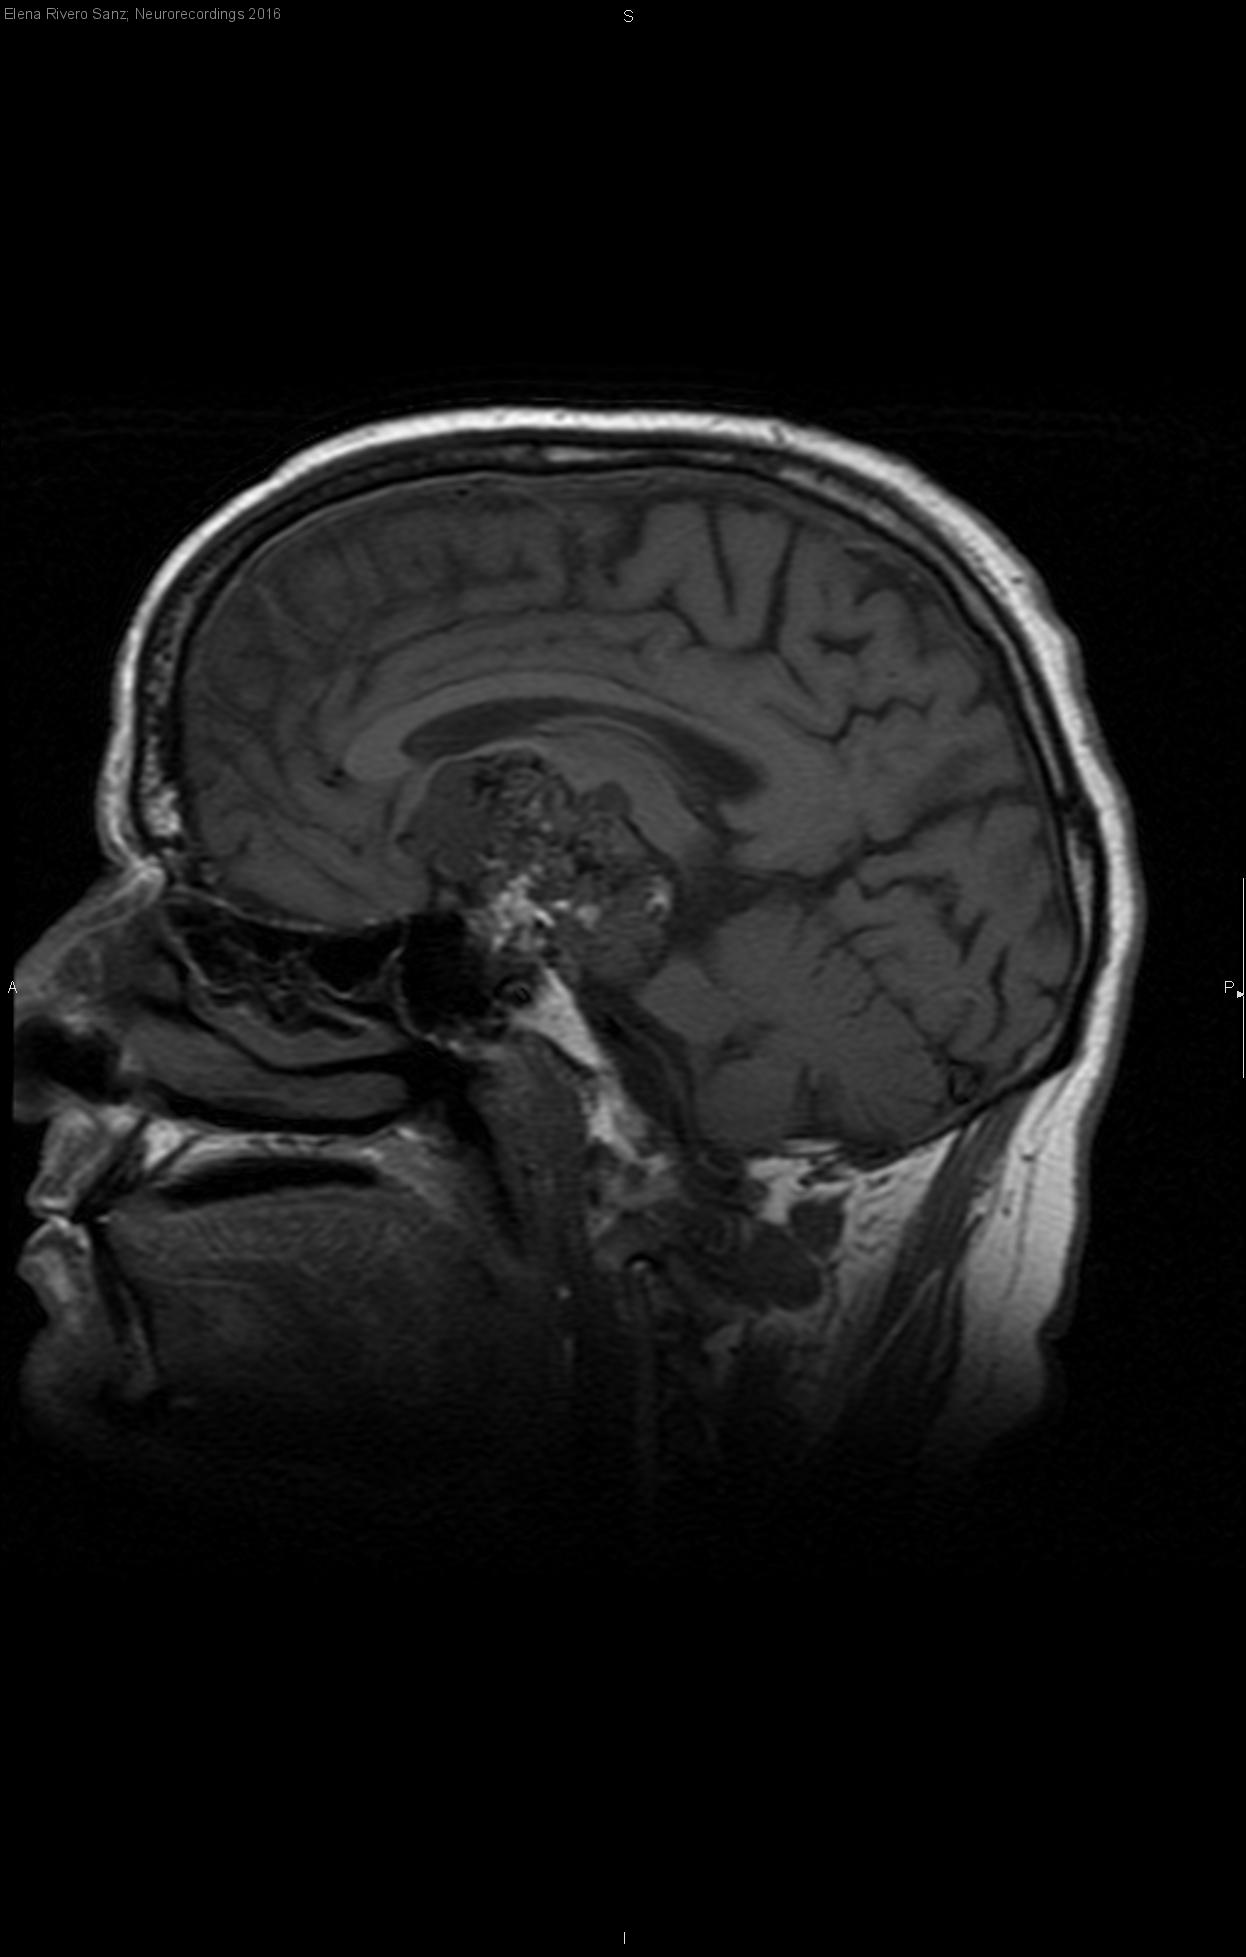

Osteocondroma de clivus en paciente joven

Hombre | 37 años

Diagnóstico final: Osteocondroma de clivus